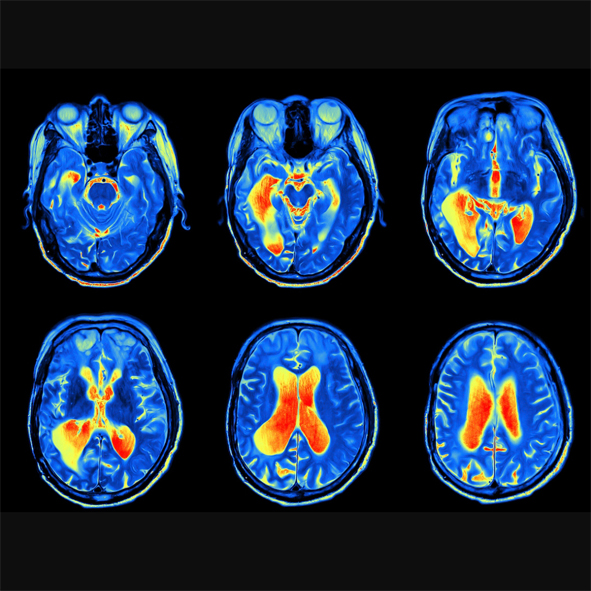

The aesthetic of these pieces is informed by: patterns in nature, Ancient mythology, Graffiti textures, Rorschach inkblot tests, 90’s dance music flyers, MRI scans and 60’s psychedelic art.